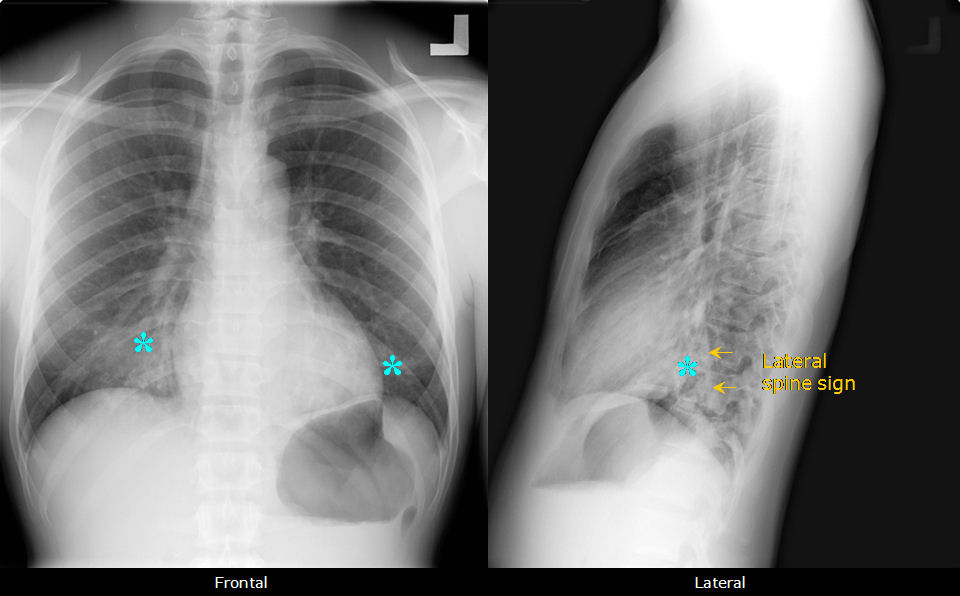

What Is A Spine Sign . spinal stenosis is the narrowing of one or more spaces within your spinal canal. aerated lung and most pleural effusions show up dark grey on ultrasound which is why the spine sign is so helpful. ankylosing spondylitis, also known as axial spondyloarthritis, is an inflammatory disease that, over time, can cause some of the bones in the spine,. what is it? the spine sign occurs when consolidation is superimposed on the spine on the lateral view with loss of the normal increased lucency of the lower. In patients without a pleural effusion.

Spine and silhouette signs due to right lower lobe pneumonia Image What Is A Spine Sign In patients without a pleural effusion. ankylosing spondylitis, also known as axial spondyloarthritis, is an inflammatory disease that, over time, can cause some of the bones in the spine,. aerated lung and most pleural effusions show up dark grey on ultrasound which is why the spine sign is so helpful. spinal stenosis is the narrowing of one. What Is A Spine Sign.